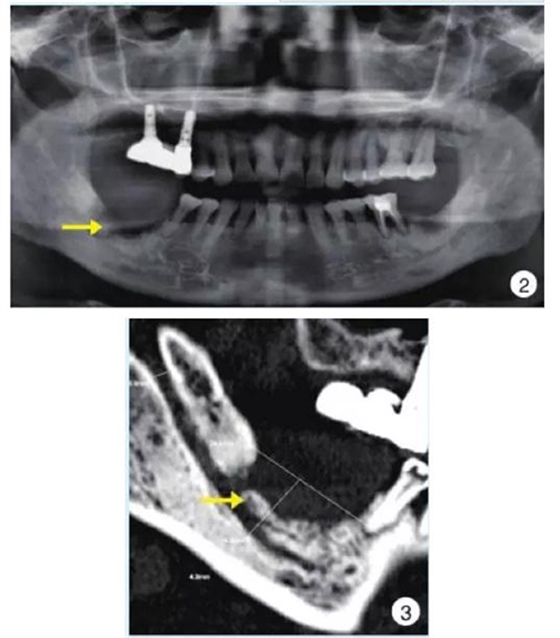

影像學(xué)早期無(wú)明顯變化,后期典型表現(xiàn)為局部片狀骨密度增高影以及不規(guī)則的骨吸收影像、死骨形成,偶爾可見(jiàn)骨膜反應(yīng);伴病理性骨折時(shí)可見(jiàn)骨折線。